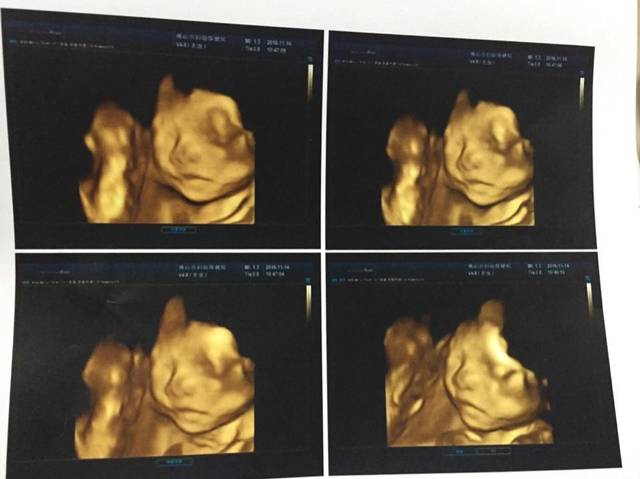

四维B超.心脏彩超和无创通过,开心开心